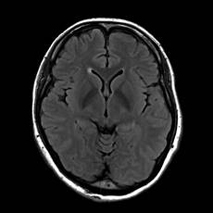

MRI(Magnetic Resonance Imaging/磁気共鳴画像)は、強力な磁石と電波を用いて体の内部を詳しく撮影する検査です。

放射線被ばくがなく痛みもない安全な検査です。通常20~40分程度で終わります。

脳だけでなく、全身のさまざまな部位の検査が可能です。

脳・脊椎・関節・四肢・腹部・骨盤・乳腺など幅広い部位に対応しています。

当院では最新の3テスラMRI装置を導入しており、従来の1.5テスラ装置とあわせて検査内容に応じた撮影を行っています。

3T MRIでは、高精細でより詳細な画像診断が可能です。

3T MRIを用いた脳ドックも行っています。

脳ドックは、脳の病気を未然に防ぐことを目的とした予防的な検査です。